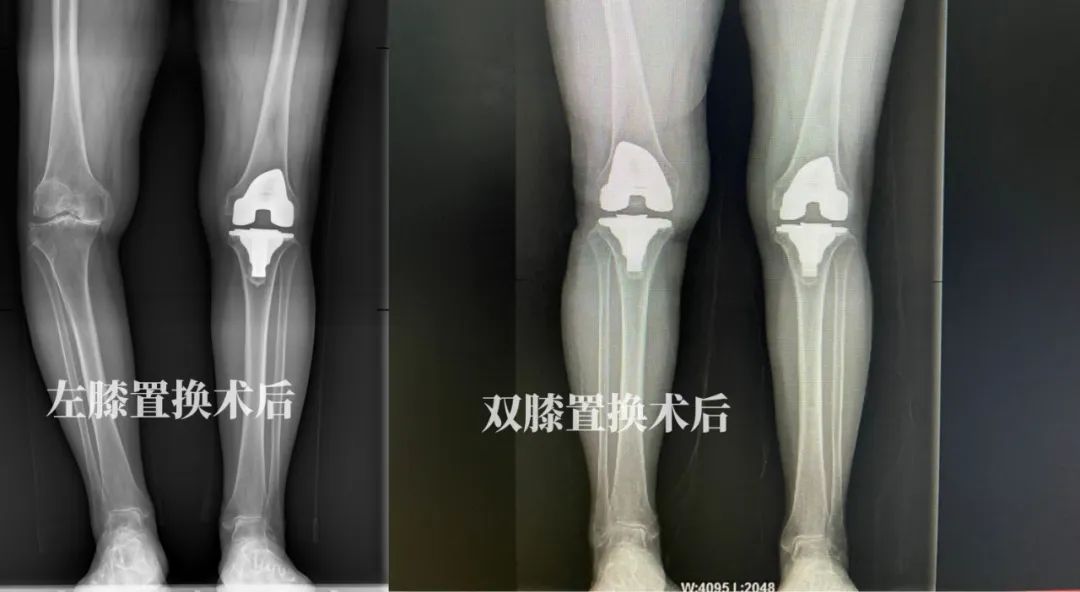

经过充分的术前准备,2022年09月28日,在徐驰主任的主刀下,为秦女士实施了左侧人工膝关节表面置换术。手术很顺利,取得了满意的效果。团队根据其康复的实际情况于2023年04月21日对其右侧的膝关节也进行人工膝关节表面置换术。

术后,秦女士在助行器辅助下,自由下地行走,然而,在术前,秦女士只能依靠轮椅,现在生活质量得到了明显提高,这对患者和家庭都是一个焕然一新的开始!